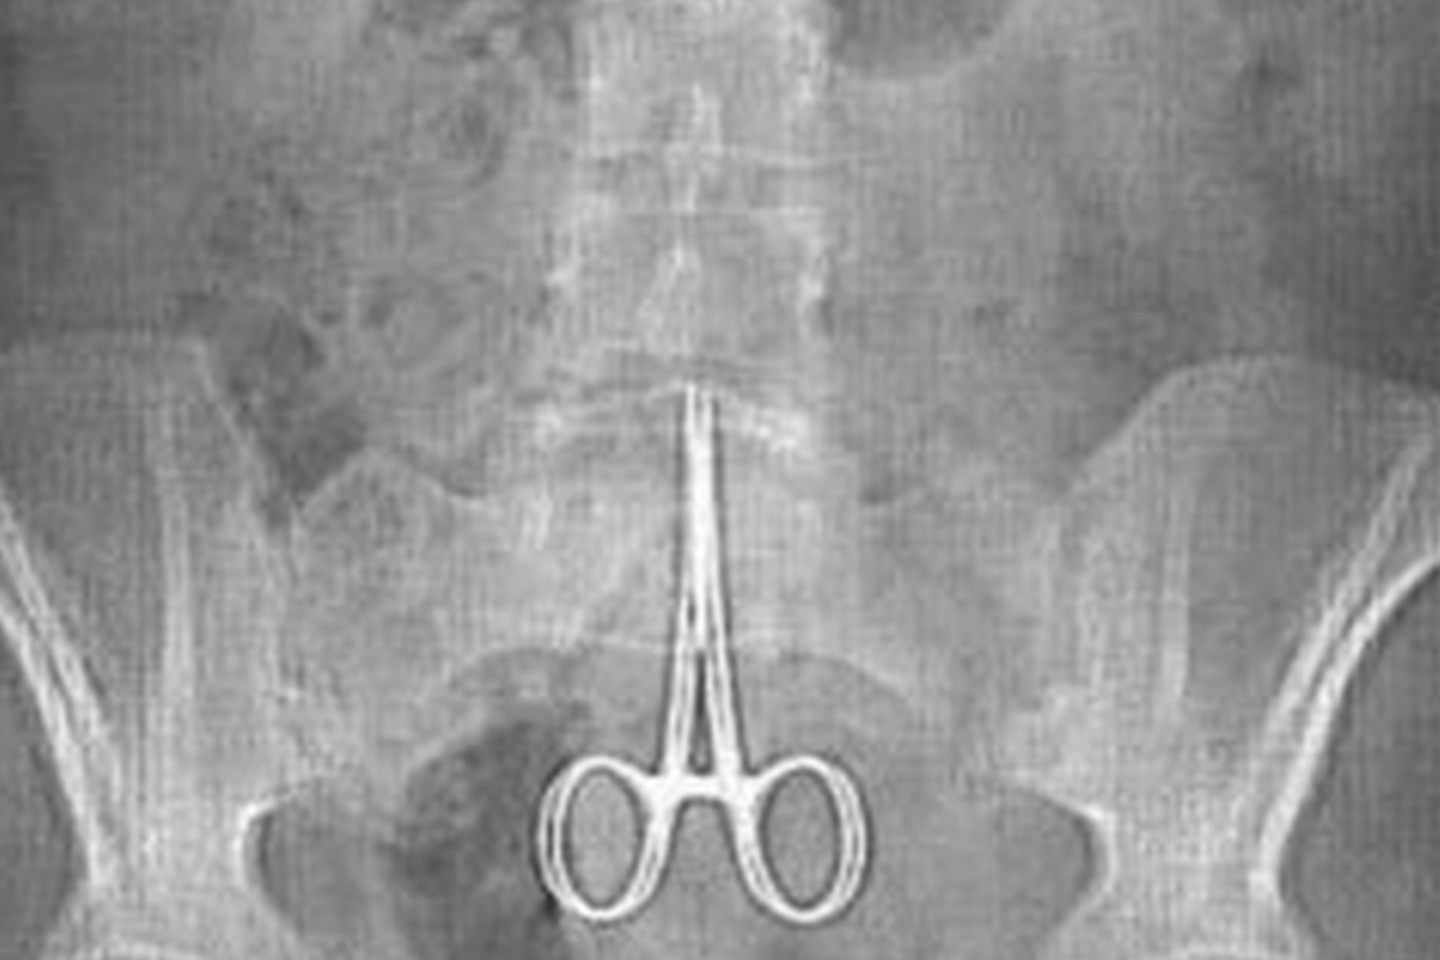

Pacientas 1998-aisiais buvo operuotas po autoavarijos. Tik visai neseniai gydytojai, atlikę tyrimą ultragarsu, jo pilve pastebėjo 15 cm ilgio žirkles. Prieš tai vyras beveik du dešimtmečius „valgė, gėrė ir gyveno gana normalų gyvenimą“.

Tačiau kažkuriuo metu jį ėmė kamuoti pilvo skausmai ir jis kreipėsi į medikus.